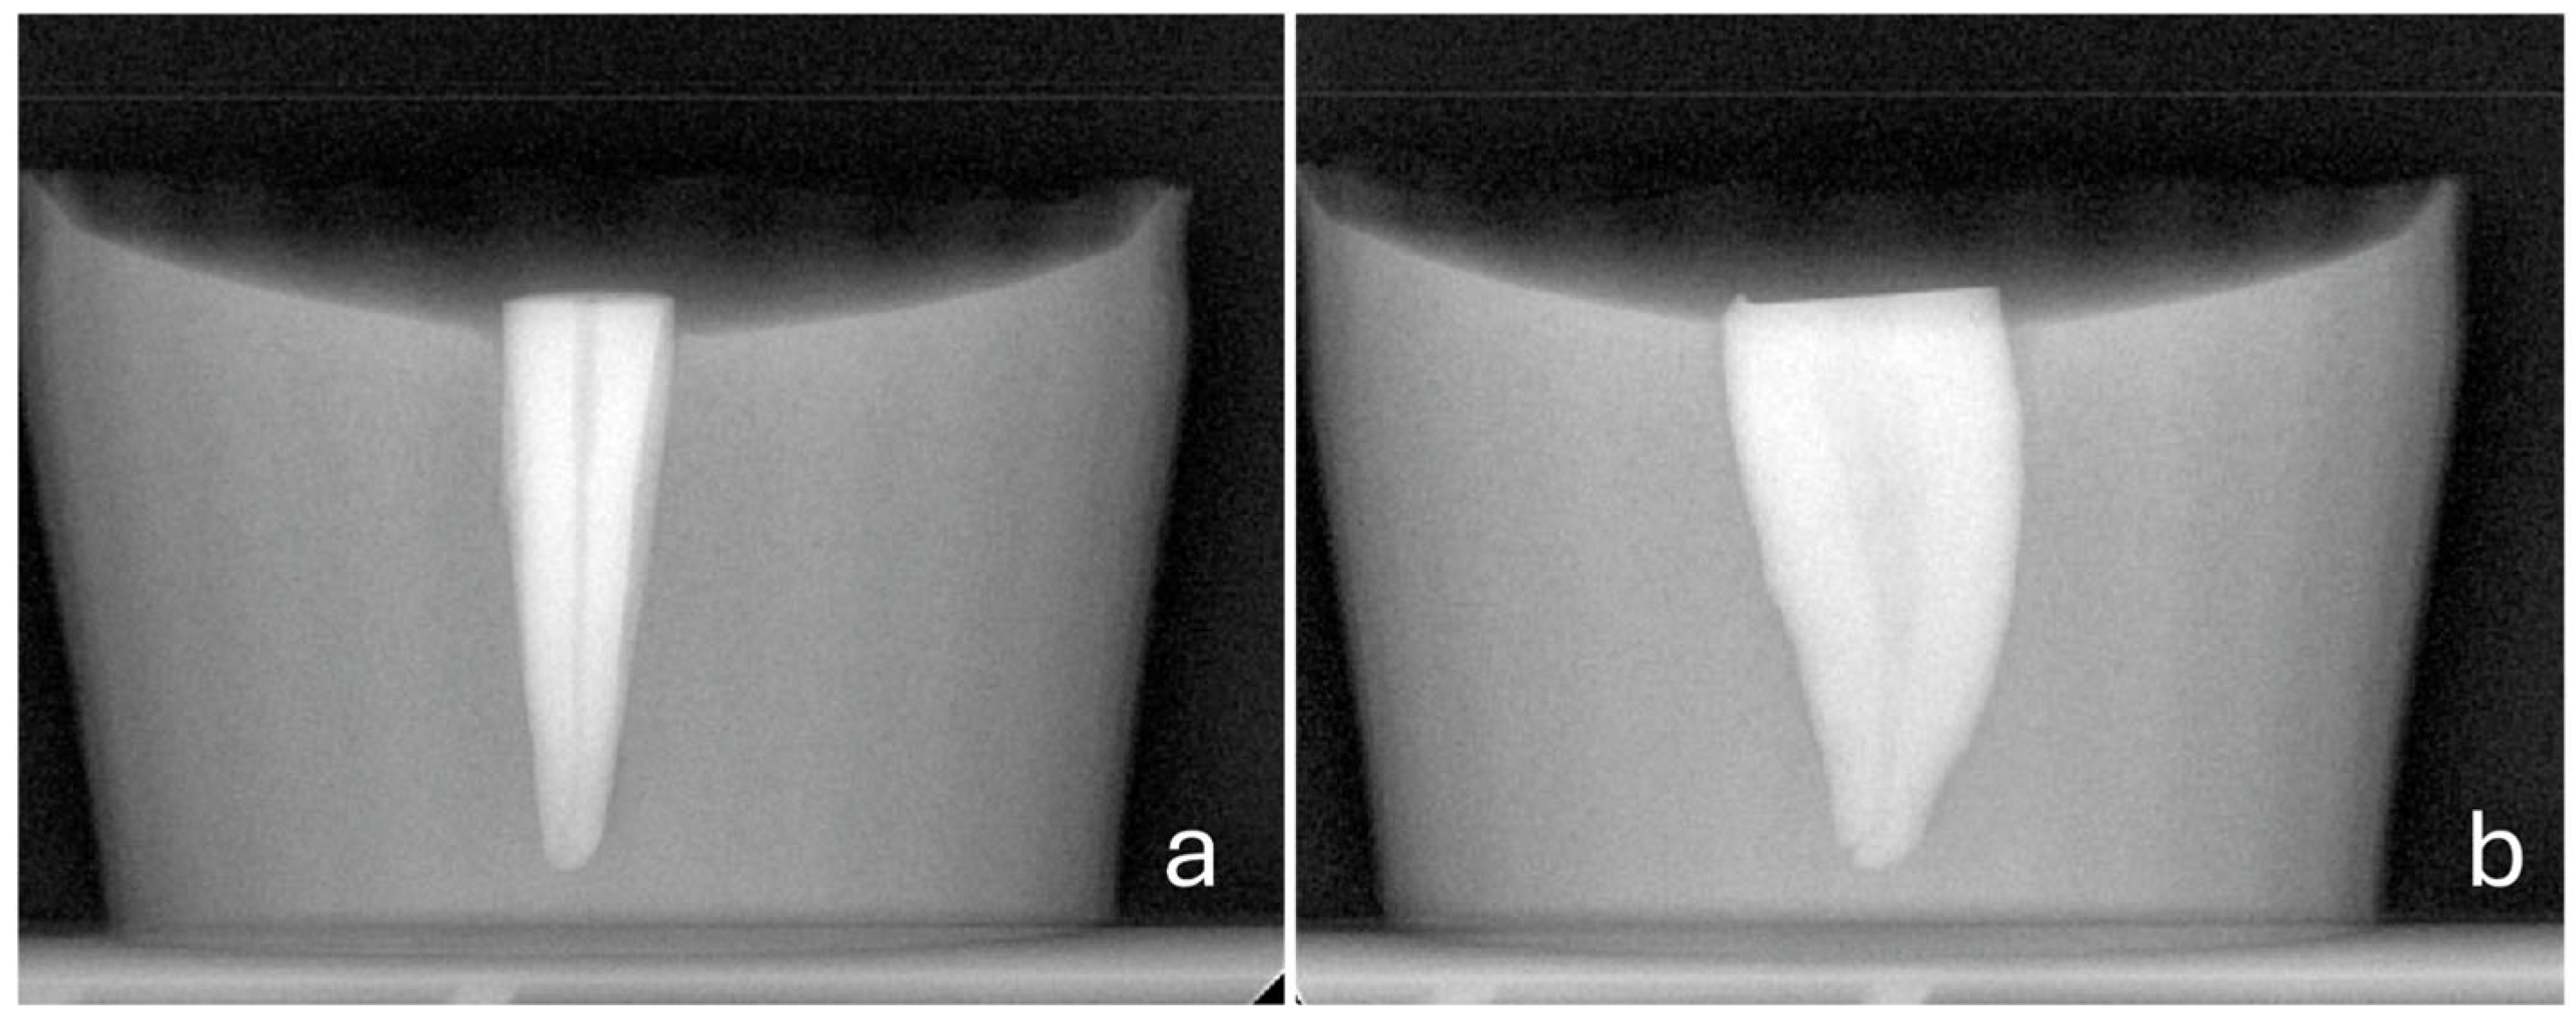

- A steady direction of perforation. Teeth were secured in a vise with their buccal surfaces parallel to the horizontal plane. The high-speed handpiece was also fixed in a horizontal position using a custom-made apparatus that allowed only downward vertical movement. Buccal diagonal perforations, starting 3 mm apical to the coronal surface of the teeth, were created under water cooling with a steady angle of 105° between the external surface of the root and the shank of the bur (Figure 2 and Figure 3). A #35-K stainless steel hand file (Dentsply, Maillefer, Ballaigues, Switzerland) inside the root canal prevented the overextension of the perforation to the lingual surface of the root.